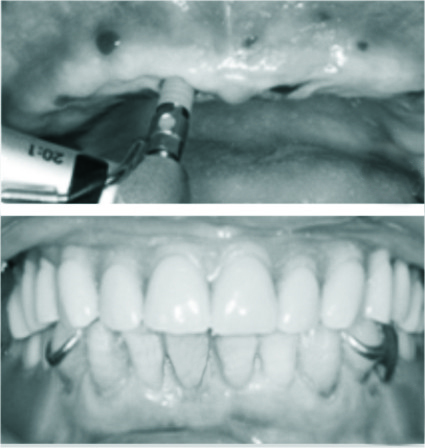

对于很多想要做种植牙的缺牙患者来说,最大的问题就是牙槽骨骨质条件差。海涛口腔“一天得”种植技术主要适合半口或者全口缺失牙的患者,以及虽有余留牙,但是牙周情况不好、牙齿松动的患者,对牙槽骨骨量没有苛刻的要求,克服了牙槽骨萎缩、骨量不足等种植难题,省去植骨这一步骤。这也自然缩短了患者的治疗周期,省去了植骨带来的额外费用,大大减轻了手术带来的痛苦。海涛口腔“一天得”种植牙技术可以做到当天种植牙根,当天佩戴全口固定义齿,当天即可吃肉。

海涛口腔突破技术壁垒,打破传统种植技术瓶颈,实现当天种牙,当天吃肉,有效节省了时间成本和经济成本,创新打造全国首家“时间服务型”诊疗体验。同时,海涛口腔的专业医师团队通过技术精研,创新降低全口种植治疗周期,无需植骨,无需增加痛苦,并采用标准化16层消毒净化系统,为患者提供专业、权威、安全、信任的服务体验。